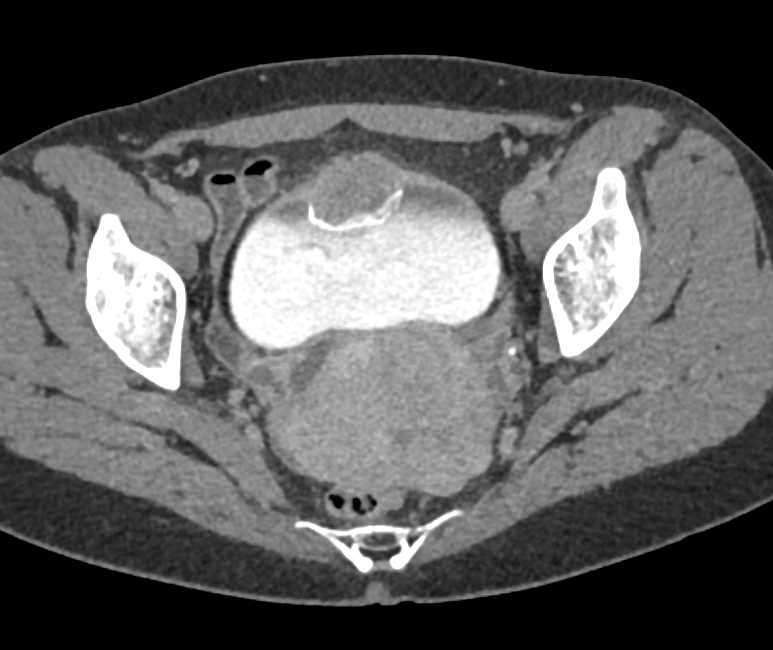

Urachal Carcinoma of the Bladder